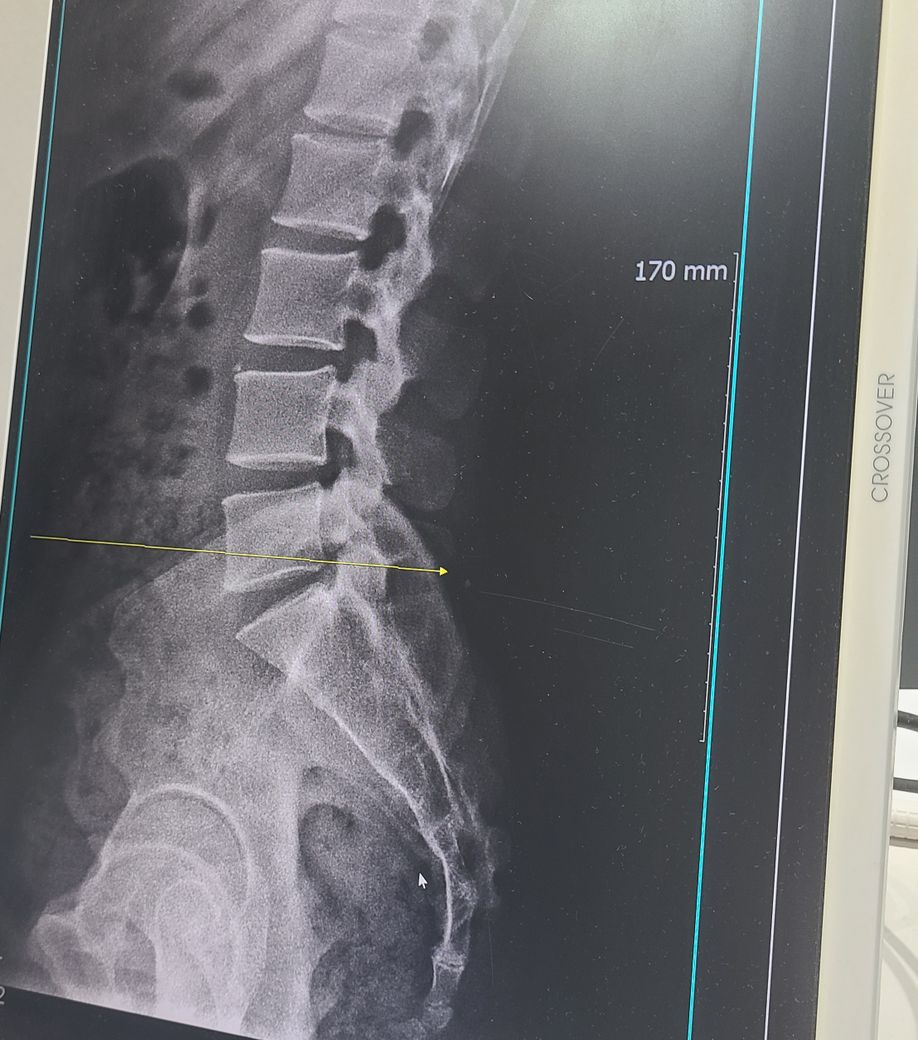

5번척추와 꼬리뼈 사이 문제인데 비만과도 연관있을까요

배가 점점 나와서 꼬리뼈가 뒤로 쳐진게 아닌건지 이런것도 영향이 있을까요 뱃살이 많을 경우 다이어트가 허리 통증에도 도움이 되는지 궁금합니다

• 1번 째 사진

상대적으로 배가 나오게되면 골반이 전방 경사되며 지금 엑스레이와 같은 형상의 척추가 나올 수 있습니다 . 배만 내밀어도 골반이 전방경사되며 허리뼈 척추 공간이 좁아질 수 있습니다. 살을빼도 좋은 방법이지만 골반의 움직임 개선이나 골반 교정이 같이 가야 허리 통증 완화에 효과가 클것으로 보입니다. 교정은 도수치료나 교정치료 받으시면 도움되실것으로 보입니다

현재로썬 엑스레이상 허리의 커브가 좀 더 있어야 할 것으로 보이고 어떤 증상으로 병원을 내원하였는진 확인이 어렵지만 꾸준한 관리와 치료를 한다면 회복 할 수 있습니다.